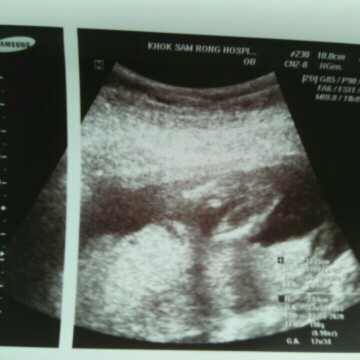

คุนแม่บ้านไหนซาวแร้วบ้างค้ะ

ดูออกไหมค้ะ ว่าเพศหญิงรึเพศชาย

บ้านนี้ก็ดูไม่ออกค่ะ แต่หมอบอกว่า ลูกสาว แม่ต้องถามหมอนะคะ ในนี้ไม่เก่งเท่าหมอค่ะ

น้องอ้าขาแบบนี้ ไม่มีอะไรยื่นออกมา ก็น่าจะลูกสาวค่ะ

ดูไม่ออกคะ ในรูปน่าจะเป็นส่วนหัวกับแขนน้อง

แบบนี้ละค่ะ พอจะเดาออกมั้ยค่ะ

น่าจะลูกสาวนะค่ะ

เดาว่าลูกสาวค่ะ